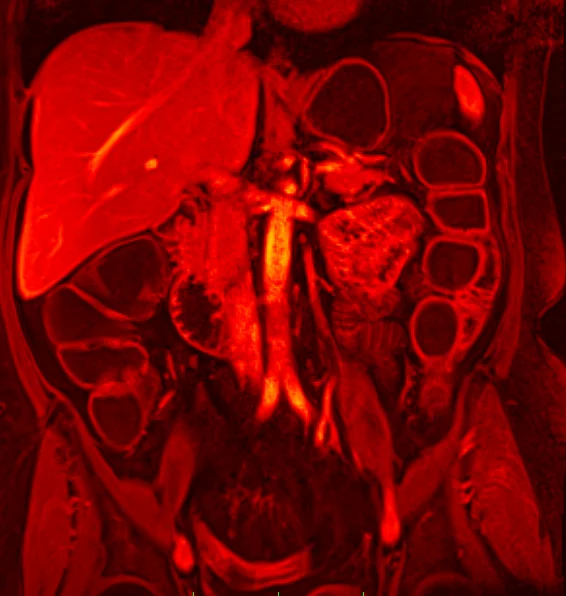

Magnetresonanztomographie: Gesamtes Spektrum der MRT-Diagnostik

- MRT Diagnostik des Halses, Brustkorbes, Bauchraumes und Beckens

- MR Angiographie des gesamten Gefäßsystems

In der Abteilung für Radiologie stehen zwei MR-Tomographen zur Verfügung. Es werden Spezialuntersuchungen wie die Ganzkörper-MRT, MR Mammographie, multiparametrische Prostata-MRT oder Kardio-MRT durchgeführt (siehe Leistungsspektrum).